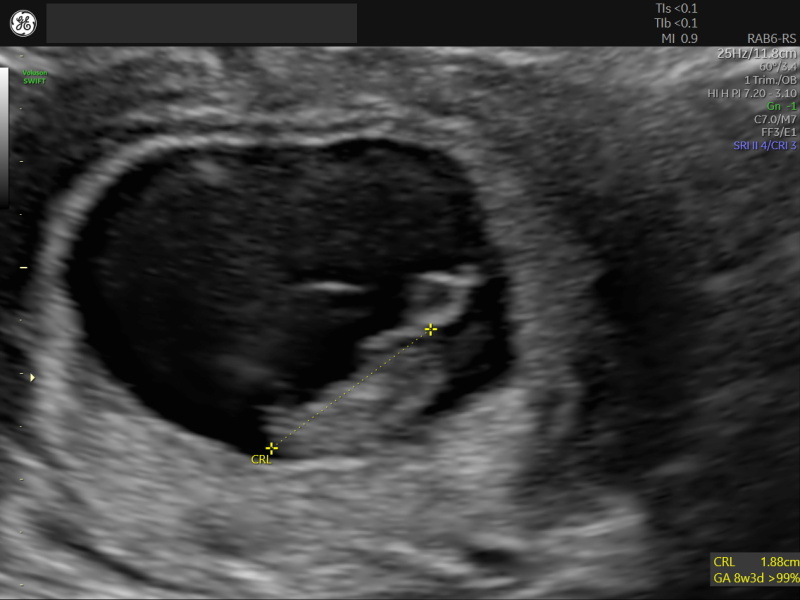

UnwieldyRhombus · 27/04/2023 23:18

Scan went well! It was such a relief. Due date is the 4th, which is what they said at the reassurance scan six weeks ago. That's 3 days earlier than the date based on LMP, but I still think I must have ovulated early, so it makes sense.

Now if the sickness and fatigue could go and I could get that second trimester boost, that would be golden!

I actually saw one of our friends (a doctor) at the hospital on my way out and literally ran up to him to show him the photos 😅